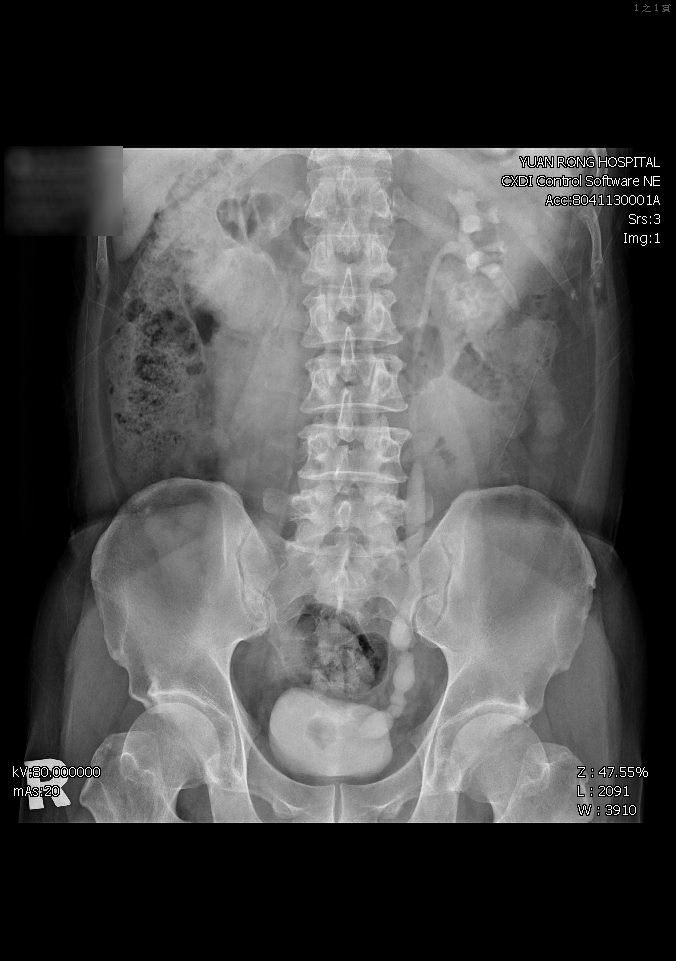

員榮醫院盧醫師聽完病情描述後安排膀胱鏡檢查,發現台商的膀胱變小及粘膜明顯乳酪狀壞死、輸尿管開口像高爾夫球洞一樣陷下去和尿道變窄等情況,懷疑結核菌感染(俗稱肺外結核),採驗結果確定「結核菌」,乃轉至胸腔科會診和治療。

感染管制師李亦晨說,結核菌須在特殊培養基中才能培養出來,一般檢查需45天至60天,但這名台商在第24天就確定為膀胱結核,醫院依規定通報衛生局,並告知台商應連續服藥6個月,院方為他做肺部X光和痰液檢查,排除肺部感染,腎功能幸未受影響。